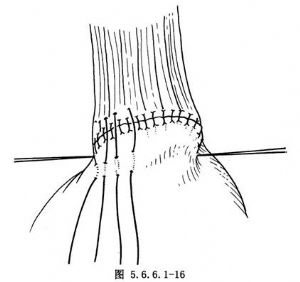

(4)常规食管胃端侧吻合:①先在预计切断食管的平面上方1cm处由食管边缘两侧分别用丝线穿过肌层与黏膜下层,与胃底部预计切开处的浆肌层缝合,两针之间的距离为食管的宽度(图5.6.6.1-10),图中食管壁上的虚线为准备切断食管的平面;②在两根缝线之间加缝数针,将食管后壁与胃底部浆肌层完全缝合(图5.6.6.1-11),图中胃壁上虚线为准备切开胃壁的部位;③切开胃壁浆肌层,但勿切透黏膜,将循行于黏膜下的每根血管用细丝线缝扎两处,然后在缝扎线之间切开胃黏膜。黏膜上切口开始不宜太大,在吻合过程中如嫌不足可再次切开(图5.6.6.1-12)。在切开胃壁之前应先用干纱垫置于吻合口后方以吸取切开胃黏膜后逸出的胃液,切开胃黏膜后迅速将吸引器头送入胃中吸净胃液;④沿预计切断食管的平面环绕食管切开肌层但勿切开黏膜,在食管肌层断面远侧约0.8cm的平面剪断食管黏膜,因留有足够的黏膜,吻合时十分便利,否则如在同一平面切断食管肌层及黏膜,由于后者的回缩使吻合操作相当困难;⑤将吻合口后壁食管全层的左右侧两角分别与胃壁切口的上缘全层用细丝线间断缝合,注意食管黏膜与胃黏膜必须对齐,缝线之间的间隔约为0.4cm,缝线结扎不能太紧以免术后局部组织水肿造成切割,成为发生吻合口瘘的主要因素(图5.6.6.1-13)。结扎线结打在腔内(图5.6.6.1-14);⑥将胃管经吻合口送入胃中,如果应用十二指肠饲食管,可在此时将引导饲食管的糖球一并送入胃中(图5.6.6.1-15),开始吻合前壁。由后壁转往前壁时,两侧转角处的缝线必须缝好,因在转角处容易发生瘘。吻合的最后4~5针最好先挂上线而不结扎,待全部缝合完毕时一次打结;⑦前壁第一层吻合完成以后,撤除原来置于吻合口后方的干纱布块,参加手术人员用无菌净水冲洗手套,将吻合使用过的器械前端用水洗净,用细丝线间断缝合吻合口前壁第二层,完成食管肌层及黏膜下层与胃底部浆肌层之间的缝合(图5.6.6.1-16);⑧将吻合口周围的胃壁用纱布向吻合口方向推送,结扎吻合口前壁第二层的缝线,使吻合口最后被套入胃壁中(图5.6.6.1-17);⑨将胃内引导十二指肠饲食管的糖球挤过幽门,清点台上敷料(包括纱布及纱垫)无误后,用中号丝线间断缝合膈肌。在胃越过膈肌处缝合不宜过紧,防止术后出现梗阻。将胃轻轻上推然后将胃壁与周围膈肌缝合6~7针,防止腹腔内脏器循此途径进入胸腔。注意不要用丝线将胃壁固定在胸壁上,此种缝线可能造成胃壁穿孔。如术者想采取措施减少吻合口的张力,可在近胃底部的胃大弯侧寻找一个切断大网膜的残结,用缝线穿过固定在纵隔胸膜上,同样可以达到吻合口减张的目的而无胃壁穿孔之虞。由第8肋间腋后线置入闭式引流管,检查胸内有无出血点或异物存留。用肋骨合并器将切口上下方的肋骨合拢,肋间组织用中号丝线缝合,冲洗胸壁肌肉,逐层关胸。将闭式引流管连接于水封瓶上。